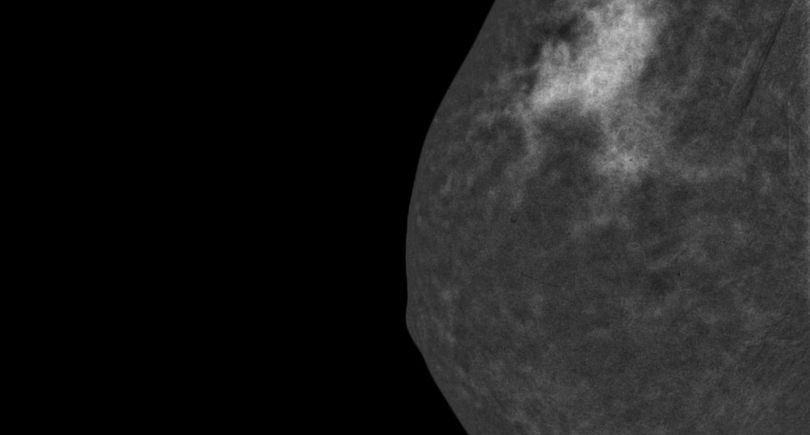

CESM is an advanced form of mammography that uses a safe dye injected into the bloodstream. This dye highlights areas of concern within the breast, giving clinicians a much clearer and more detailed image than a traditional mammogram.

“Sometimes it can be difficult to interpret a mammogram, especially in patients with dense breast tissue”, Nicole explains. “It’s a bit like looking for a cloud in a sky full of clouds. The contrast helps remove that ‘noise’ and shows us exactly what’s going on inside the breast.”

“A patient came to us with a lump in one breast. When we used CESM, we also spotted abnormality in the other breast. This enabled both breasts to be dealt with at the same time which would not have been possible otherwise.”